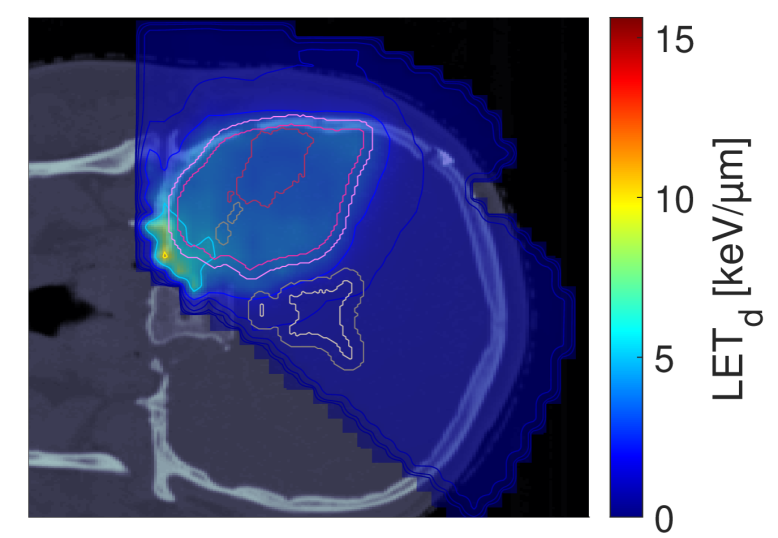

Figure 2 shows the optimal slice images of the dose (left), dose-averaged LET (middle) and POLO distribution (right). On the underlying CT scan, the tumor volumes are marked by violet to purple contours, while the VS (ventricles and 4 mm4\text{\,}\mathrm{mm} fringe) is outlined in white and gray. We observe the high-dose region covering all of the GTV, with a largely homogeneous transition to the clinical and planning target volumes (CTV, PTV), and a moderate to severe overlap to the VS. The dose-averaged LET distributes in layers, with increased values around the contour edge of CTV/PTV and local peaks at the distal ends of the proton beams. Accordingly, hot spots on the POLO map are found in regions where dose and dose-averaged LET scale up, or close to the VS. Beyond the PTV, the POLO map reveals cold spots, due to the steepness of the dose and dose-averaged LET gradients.

dRBE,fxd_{RBE,fx}ABCD ldl_{d}ABCD ppABCD

Refer to caption Refer to caption Refer to caption

NTCP:45.59 %NTCP:$45.59\text{\,}\mathrm{\char 37\relax}$ABCD

Figure 2: Optimal 2D slice images of the RBE-weighted fractional dose dRBE,fxd_{RBE,fx}, the dose-averaged linear energy transfer ldl_{d} and the probability function values pip_{i} for the baseline plan. The dose distribution (left) shows high target coverage with decreasing exposure beyond the CTV/PTV margins, but also visibly overlaps with parts of the VS. Meanwhile, for the dose-averaged LET (middle), layered homogeneity in the target volumes and local maxima at the distal ends of the proton beams can be observed. This results in more pronounced levels of POLO values within the target volumes, particularly in the presence of local dose-averaged LET maxima and in the environment of the VS. Referring back to the POLO model from Equation 1 and (3), we can expect exactly this type of coherence between the model output, the physical input feature profiles and the increased local risk near the VS. The baseline treatment plan exhibits a complication risk of 45.59 %45.59\text{\,}\mathrm{\char 37\relax} after evaluation of the POLO distribution with NTCPpNTCP_{p}.